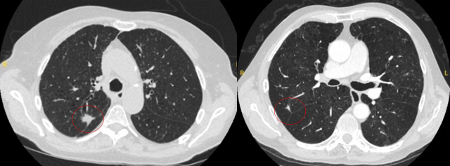

The appearance of the adjacent fissure, as well as any visible pleural ‘tags’, are signs that need to be considered when evaluating perifissural or peripheral solitary lung nodules. A retracted fissure associated with a non-smooth nodule increases the possibility of malignancy.[33][34][Figure caption and citation for the preceding image starts]: Computed tomography (CT) sections from two cases with benign perifissural nodules. Note the smooth margins and the normal undisturbed adjacent fissureFrom the collection of Dr George Tsaknis, MD, PhD, FRCP(London), MRQA, MAcadMEd, PGCert; used with permission [Citation ends].

[Figure caption and citation for the preceding image starts]: Computed tomography (CT) showing examples of malignant perifissural nodules. Note the spiculated edge of the nodules and the evident retraction of the adjacent fissure. Both resection tissue analyses confirmed adenocarcinoma of lungFrom the collection of Dr George Tsaknis, MD, PhD, FRCP(London), MRQA, MAcadMEd, PGCert; used with permission [Citation ends].